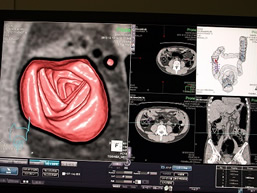

大腸CT検査

| 大腸CT検査 | 24,420円 | 大腸に炭酸ガスを注入し、拡張させCTで撮影、その後コンピューターで画像解析を行うことで、大腸内視鏡や注腸検査に似た3次元画像を得て診断をする検査です。 *人間ドック健診とは別日に実施する検査となります |